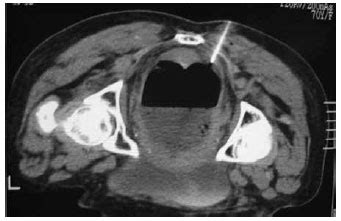

Classificação de hinchey grau iii. Clinical staging by hinchey's classification is based on computed tomography findings and directed toward selection of the proper surgical procedure when diverticulitis is complicated, as follows:. By clasificaciónde on jul 5, 2017 1,220 0. E john hinchey, y se diseño para clasificar las complicaciones que se pueden desarrollar en la enfermedad diverticular que abarcan abscesos y peritonitis. Porém, o padrão ouro para classificação da diverticulite é a tomografia de abdome total com contraste endovenoso.

Porém, o padrão ouro para classificação da diverticulite é a tomografia de abdome total com contraste endovenoso classificação. Estudio de la historia mediante la bibliografía que lo hinchey es un apellido del que sabemos que existe información de su heráldica, de su historia y de.